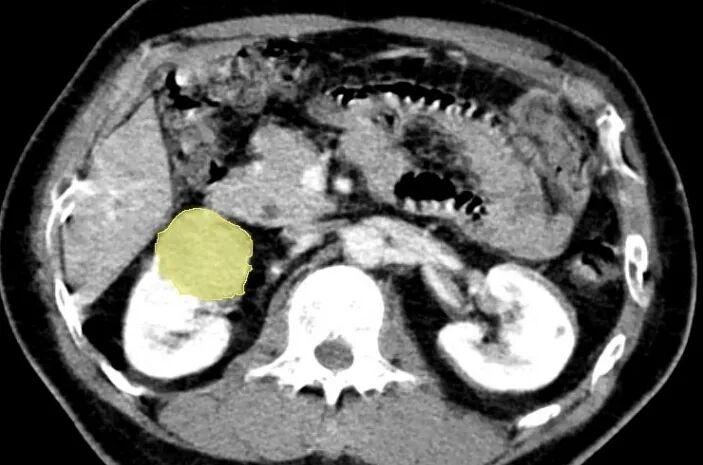

基本信息:患者右肾见约39*36mm肿瘤,考虑肾癌可能;两肾多发囊肿,左肾上腺内侧支结节,考虑腺瘤可能。

CT扫描中,识别出7个病灶

其中最大肾肿瘤(约39*36mm)

三维重建中病灶位置信息